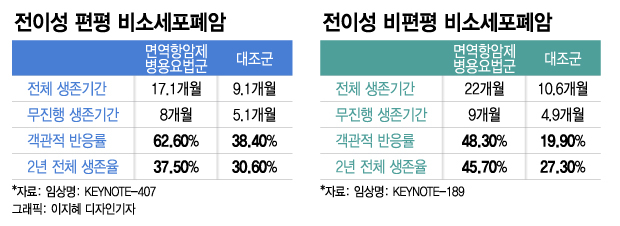

첫 번째 단계는 유전적 돌연변이에 맞는 약물을 찾는 것이지만, 유전적으로 맞지 않더라도 면역치료나 표적치료제는 사용할 수 있다. (여기서부터는 경제적 측면과 관련이 있습니다.) 이런 표적치료나 치료를 받으면 이전보다 상당한 기간 동안 더 나은 반응을 유지할 수 있다고 합니다. 아무튼 기대됩니다~~!!!!

그리고 사실 3월 1일부터.. 키투르다가 폐암 1차 비소세포치료제로 급여된다는 소식~~ 너무 반가워요!!!

기사를 참고해주세요. 키트루다는 2017년 8월 비소세포폐암 1차 치료제로 등재됐으며, 2018년 2월 흑색종까지 보장범위를 확대했다. 이번에 확대된 보장범위는 ▲1차 치료제 단독요법이다. PD-L1 유전자 발현, EGFR 또는 ALK 변이가 없는 진행성 비소세포폐암 ▲ EGFR 또는 ALK 변이가 없는 전이성 비편평 비소세포폐암의 1차 치료를 위한 병용요법(키트루다+페메트렉시드+백금화학요법) ) ▲ 1차 전이성 편평비소세포폐암 병용요법(키트루다+카보플라틴+파클리탁셀) ▲ 자가 조혈모세포 이식 실패 또는 이식 불가 2회 이상 치료 후 진행된 재발 불응성 고전적 호지킨 림프종 등 (출처) 키트루다 원발성 폐암 급여 확대 예상 비용 1,762억원 | 작성자 뉴스 더보이스 우리엄마~ 진단받고 3주째 기다리셨는데… 소화가 안되시네요… 기침이 나고… 잠도 못잤어요… 그런 말을 할 때마다 마음이 가라앉는다… 그래도 의사선생님을 믿고 신뢰하며 면역력을 키우기 위해 최선을 다하겠습니다. 폐암4 기분 좋아~!! 우리 모두 함께 냄비를 만들어보자!!! #폐암4 #폐암진단, #폐암싸움, #폐암치료, #폐암면역치료, #면역력강화, #자폐증응원, #키투르다, #여수건강, #여수약국, #한약약국, # 여수헬스케어